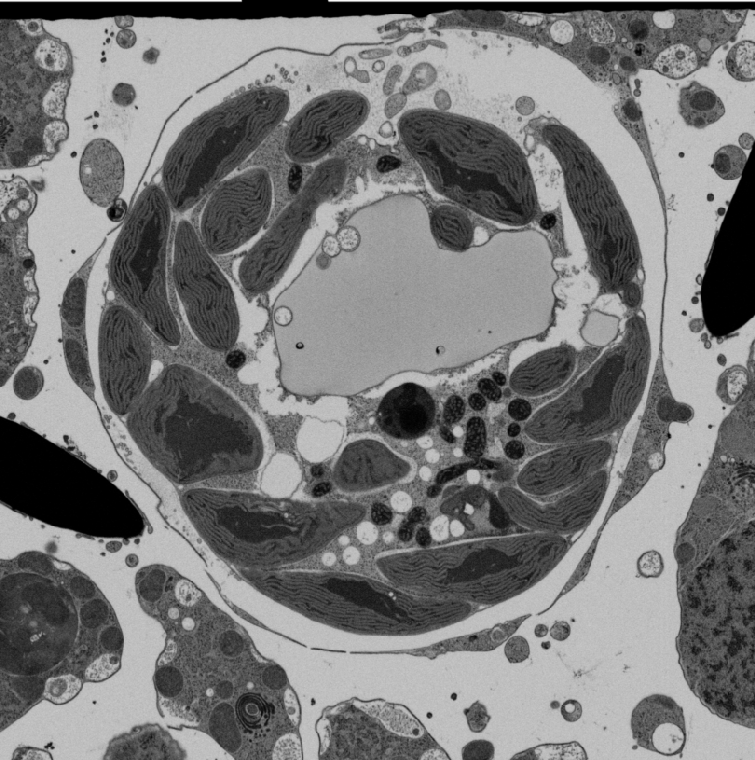

Actual z-index: 295Sampling: sampled from 584 source slicesScale: 20 x 20 x 20 nmContrast: source uint8. 8-bit source planes are written directly without intensity renormalization.Frame cache: warming 0/96Keyboard: ←/→ step, Home/End jump.